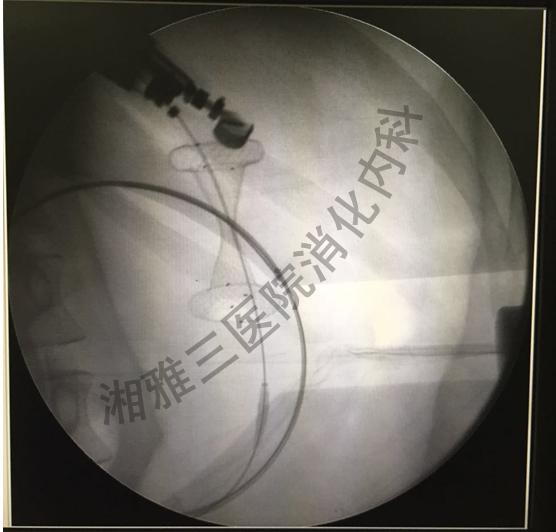

患者为青年女性,因坏死性胰腺炎合并胰腺假性囊肿4月入院,CT提示胰腺假性囊肿最大长径约10cm。近期囊腔明显增大出现压迫症状,导致患者无法进食,明显消瘦。3月20日王晓艳主任带领消化内科超声内镜团队采用双蘑菇头覆膜金属支架为患者实施了EUS引导下假性囊肿引流。基于本学科非常成熟的假性囊肿支架内引流技术,术中王主任及助手准确将双蘑菇头支架释放于囊腔及胃腔之间,大量浑浊囊液即刻通过支架涌入胃腔,患者囊肿明显缩小,腹胀、气促症状消失,目前恢复良好,近期将顺利出院。

循证医学显示EUS引导下假性囊肿引流术是治疗假性囊肿首选的方法,与外科手术比较,具有手术时间短、并发症低、痛苦小、恢复快的优势。以往假性囊肿引流支架会移位进入胃腔、囊腔,严重时需外科手术取出。双蘑菇头金属支架两端类似膨大蘑菇头,能更好得固定于胃壁和囊腔之间,移位风险明显减少,且可通过其进行进一步内镜清创。置放双蘑菇头支架对内镜技术、支架置放水平要求更高,目前国内仅有少数几家医院开展。此次消化内科成功完成湖南省首例超声内镜引导下双蘑菇头支架引流胰腺假性囊肿,标志着消化内科胆胰微创诊治水平又迈上新台阶,将为广大胆胰患者带来福音。